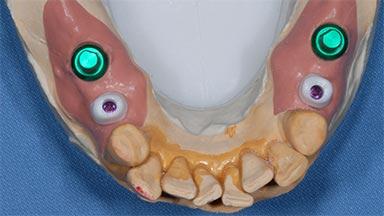

Replacement of Multiple Teeth in a Partially Dentate Posterior Mandible with a Fixed Dental Prosthesis Using a Flapless Approach

# of Teeth 4

# of Implants 4

Type of Implants One-Piece|Two-Piece

Attachment One-Piece|Two-Piece

Prosthesis Type FDP